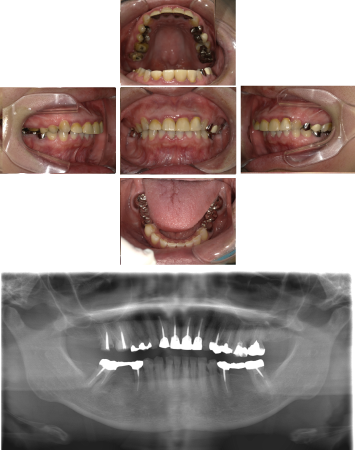

インプラント治療(左上5ソケット・GBR 右上2左上13GBR)

| 年代・性別 | 50代・男性 |

| 主訴 | 入れ歯だと咬めなくてつらい。 |

| 部位 | 上顎②1①2③4⑤Br |

| 治療期間 | 約9ヶ月 |

| 費用 | ¥1,794,100(税込) |

| 副作用・リスク |

|